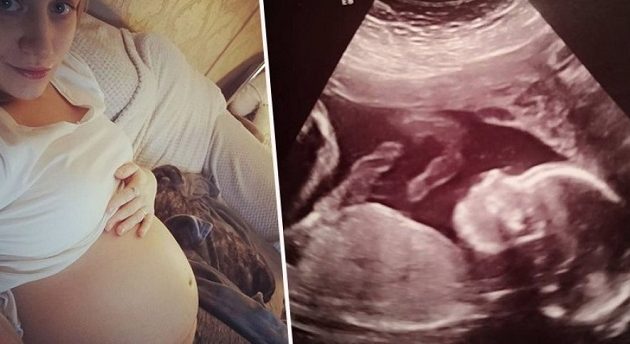

Μια απίστευτη ιστορία με αίσιο τέλος έλαβε χώρα πριν λίγο καιρό στο Έσσεξ της Αγγλίας όταν δύο νεαροί γονείς κλήθηκαν να αποφασίσουν για το μέλλον της ζωής του αγέννητου μωρού τους.

Βέλγοι χειρουργοί επιχείρησαν μια πρωτοποριακή επέμβαση κατά την οποία έβγαλαν από τη μήτρα της μητέρας το μωρό της για να το θεραπεύσουν από μια απειλητική για τη ζωή του αρρώστια και στη συνέχεια το επανατοποθέτησαν πίσω για να ολοκληρωθεί η κύηση!

Το αγέννητο κοριτσάκι ήταν μόλις 20 εβδομάδων όταν το υπερηχογράφημα Β΄ επιπέδου της Μπέθαν Σίμπσον από το Έσσεξ εντόπισε ένα πρόβλημα που είχε στην σπονδυλική του στήλη.

Το έμβρυο είχε μια γενετική ανωμαλία, που ονομάζεται spina bifida (δισχιδής ράχη) η οποία επηρεάζει τον νωτιαίο μυελό και εμποδίζει τη σωστή ανάπτυξη.